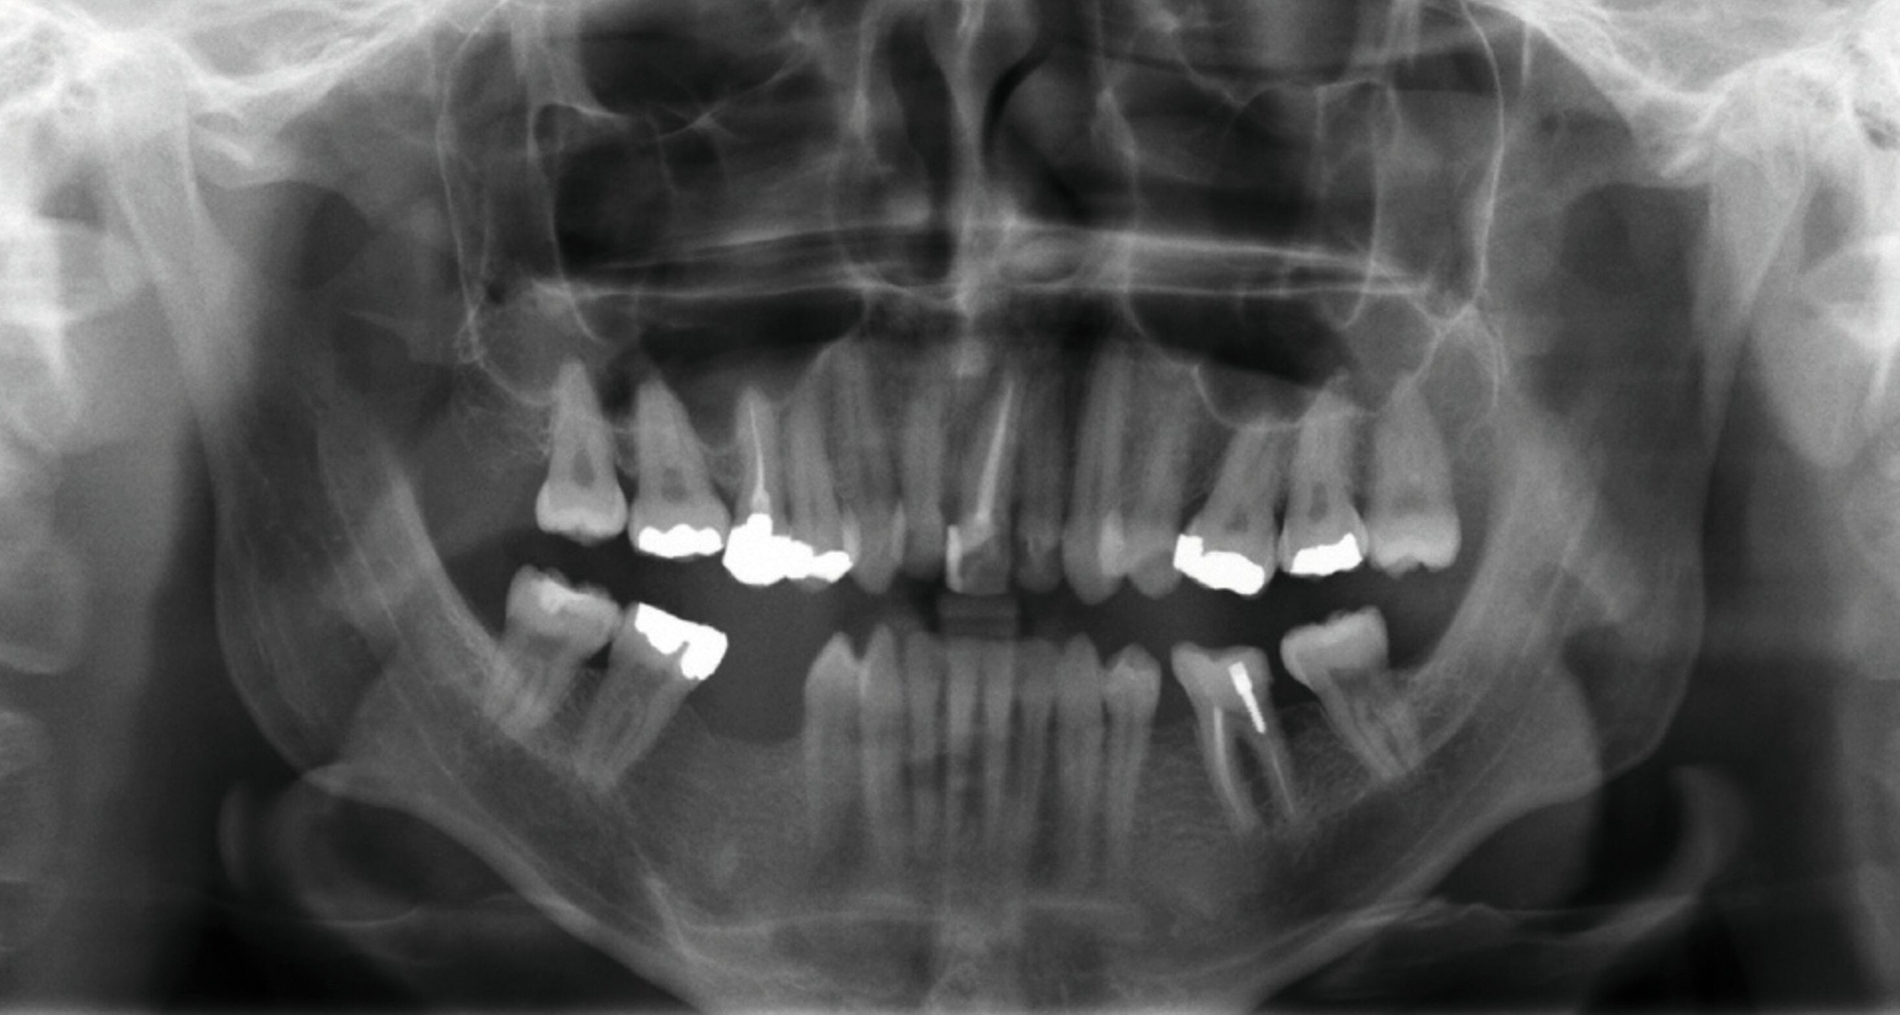

Ein 25-jähriger Patient stellte sich mit dem Wunsch nach Optimierung seines Erscheinungsbildes und seiner Kaufunktion in der kieferorthopädischen Praxis vor (Abbildung 1). Klinisch zeigten sich eine Angle-Klasse-III-Verzahnung mit einer 3/4 Prämolarenbreite Mesialokklusion beidseits und ein zirkulärer Kreuzbiss von 18–12/48–41 und 21–28/31–37. Es lagen ein negativer Overjet von -6,7 mm und ein Overbite von 5,1 mm vor. Eine Mittellinienverschiebung wurde sowohl im Oberkiefer – mit einer Abweichung von 4 mm nach rechts – als auch im Unterkiefer – mit einer Abweichung von 3 mm nach links – diagnostiziert (Abbildungen 2 und 3).

Aufgrund einer hohen Kariesanfälligkeit und einer klinisch floriden Parodontitis waren bereits mehrere Zähne des Patienten extrahiert worden, darunter 16, 11, 25, 38, 35, 45 und 46. Die mesiale Kippung und Aufwanderung der angrenzenden Zähne ließ vermuten, dass der Zahnverlust zeitlich weiter zurücklag. Aufgrund der reduzierten Langzeitprognose des Zahnes 11 entschieden wir uns gemeinsam mit dem Patienten für eine Ausgleichsextraktion des Frontzahns.

Außerdem wurde vor der kieferorthopädischen Intervention die Parodontitis vom Hauszahnarzt behandelt, so dass im Anschluss eine Multiband-Apparatur im Ober- und im Unterkiefer eingesetzt und die Zahnbögen nivelliert werden konnten. Dabei wurden die seitlichen Schneidezähne 12 und 22 anstelle der Zähne 11 und 21 lückig eingeordnet. Die Lücken in Regio 35 und 45 wurden für eine spätere Versorgung vorbereitet.